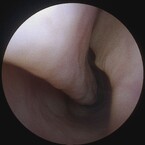

Deviated Nasal Septum

Deviated Nasal Septum is a significant shift in the nasal septum which can obstruct sinus drainage and airflow, contributing to sinus infections and congestion and sometimes nosebleeds, and snoring . A surgical procedure called septoplasty is done to correct this issue. A hole or opening in the nasal septum is called a Septal Perforation a condition that may result from various causes such as trauma, certain medications, underlying medical conditions or cocaine use. Even though conservative treatments can help manage this problem, surgical correction offers a permanent resolution.